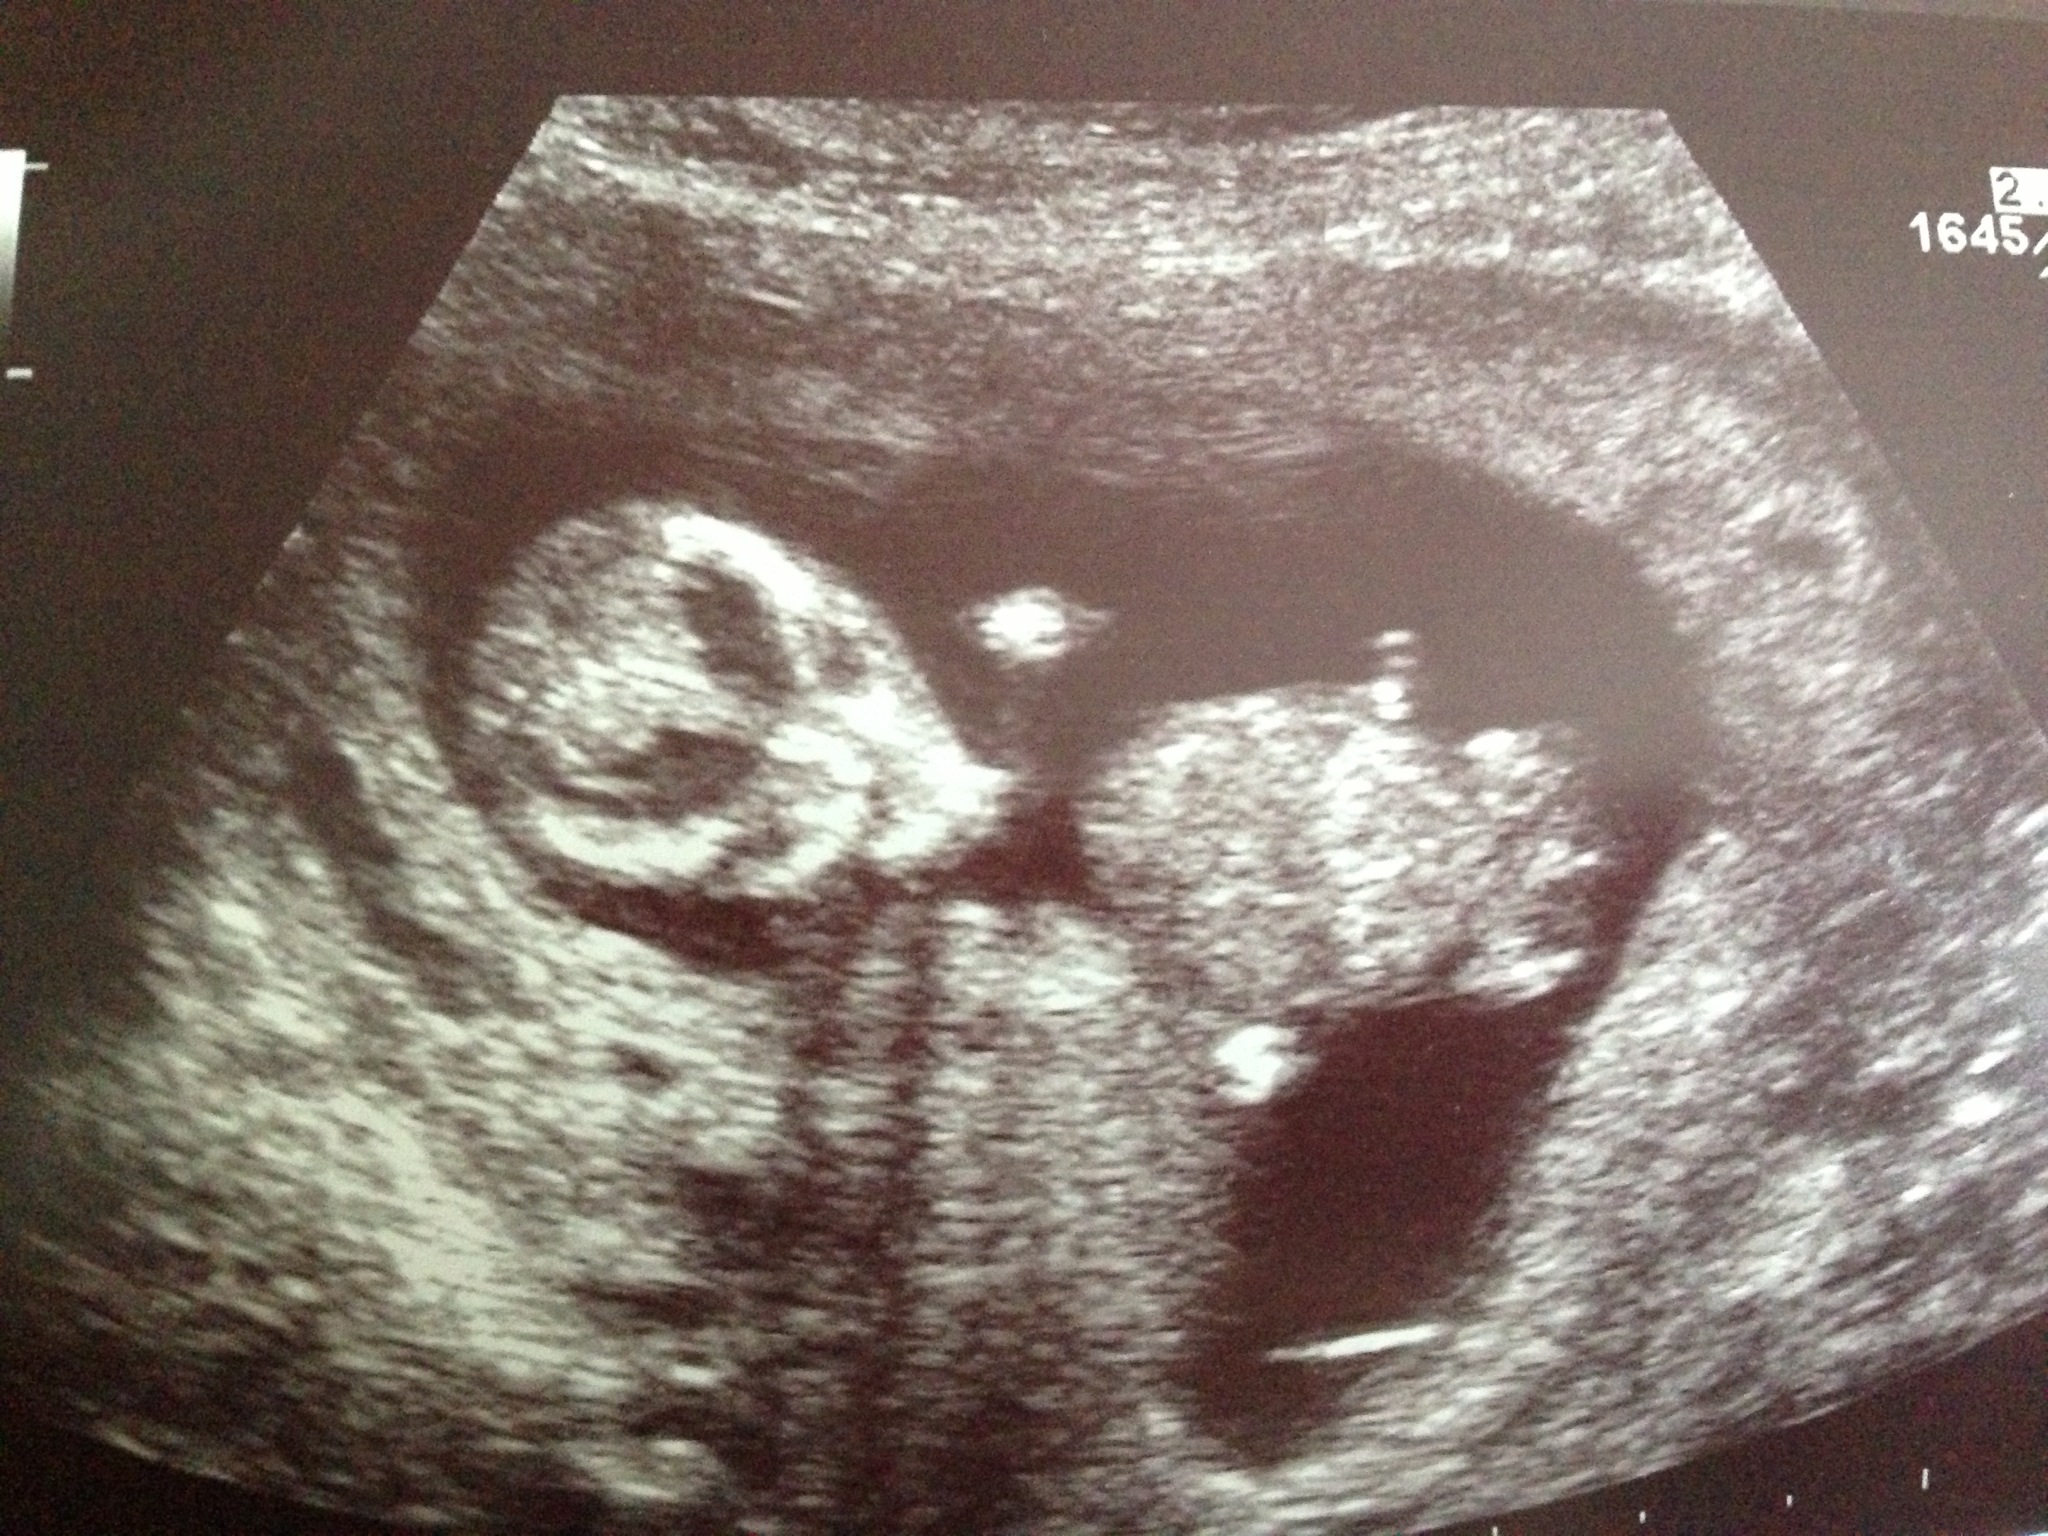

Attachment 15030Attachment 15031

Boy, I'd say

The skull looks more boy.